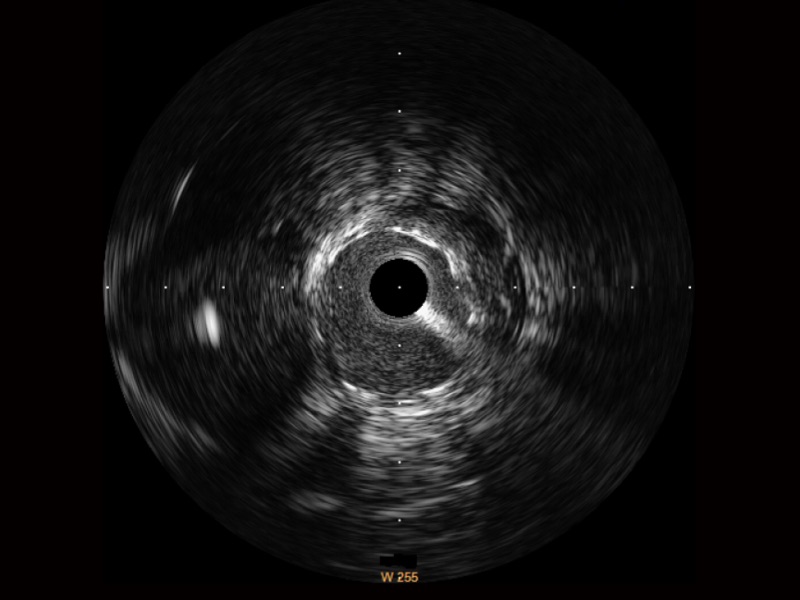

傳統(tǒng)IVUS圖像

對比傳統(tǒng)IVUS導(dǎo)管成像,開立寬頻IVUS圖像的近場支架梁顯影更細(xì)膩,遠(yuǎn)場中膜外血管仍清晰可辨,兼顧遠(yuǎn)中近,兼顧分辨力與穿透深度